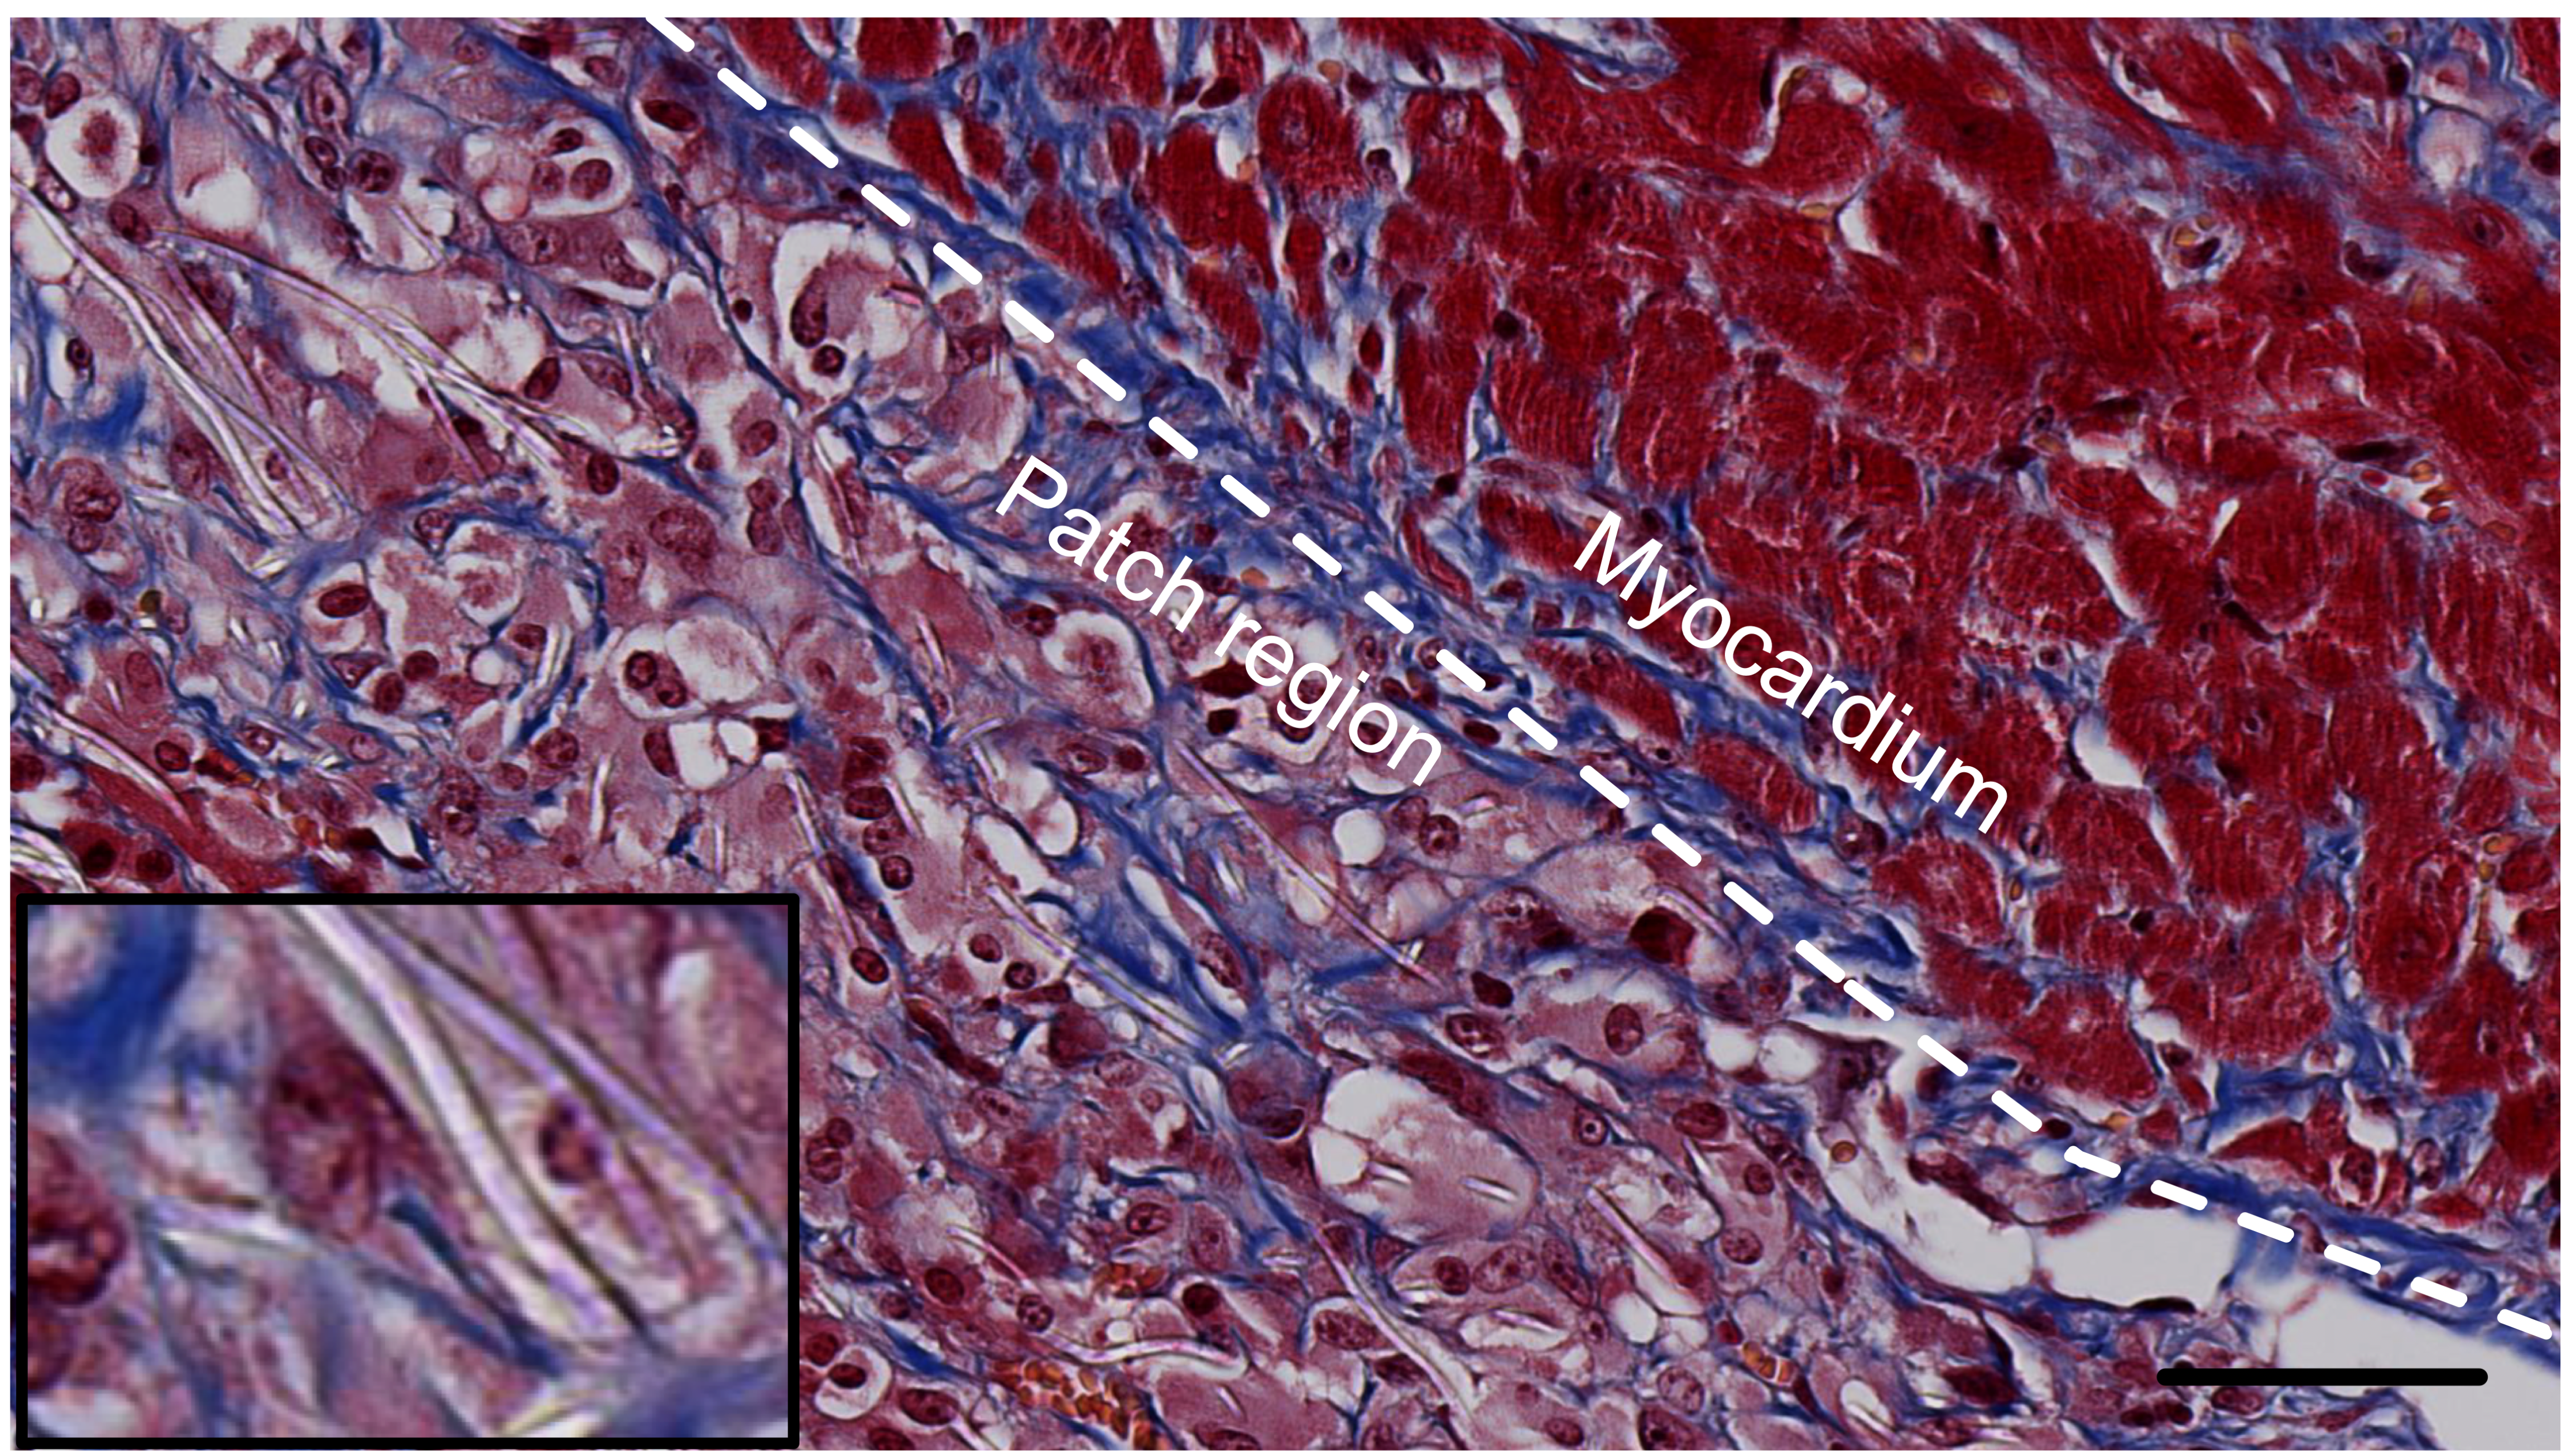

Nova tecnologia usa os batimentos cardíacos para curar o coração